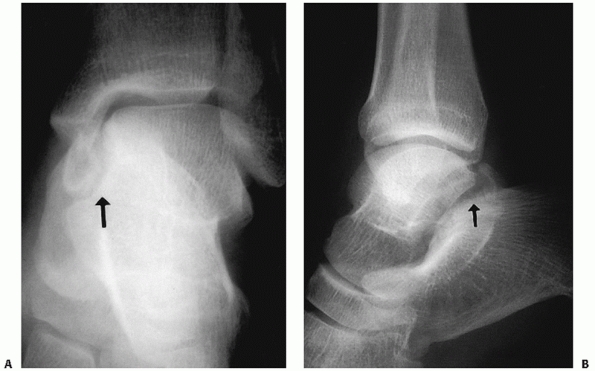

FIGURE 58-2 Intraoperative fluoroscopic evaluation of the talus. A. A Canale and Kelly view and lateral image of the subtalar joint. B. Lateral and anteroposterior views of the ankle in a talar neck fracture with an associated lateral process fracture.

FIGURE 58-4 Displaced Hawkins’ type II fractures of the talar neck with subluxation (A) and dislocation (B) of the subtalar joint.

FIGURE 58-5 Displaced fracture of the talar neck with dislocation of both the subtalar and tibiotalar joints (Hawkins type III).